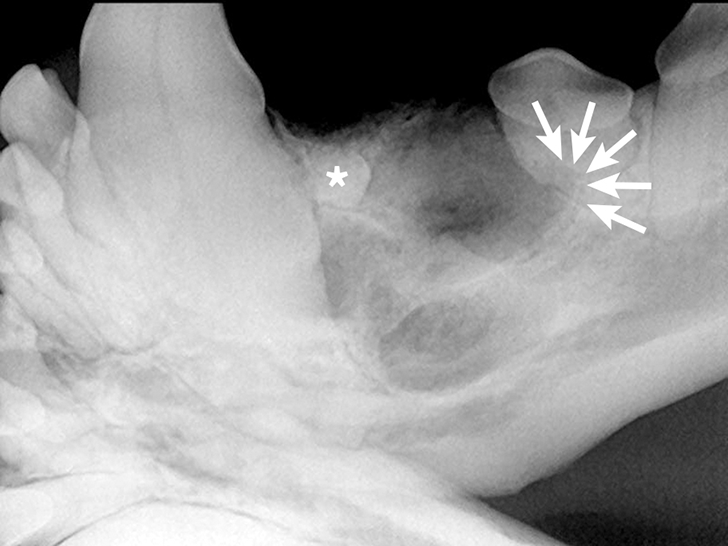

Multiple Oral Pathologies in a Dog Clinician's Brief Epistaxis Dog Clinician's Brief The face should be examined for visual or palpable asymmetry and bony. The dog is an indoor pet that only goes outside. Here are some tips to get the. Leishmaniasis, ehrlichiosis, rodenticide toxicity, immune. So, you are at home with your pet and a bloody nose starts and does not seem to be stopping. Epistaxis is one of the most. Epistaxis Dog Clinician's Brief.